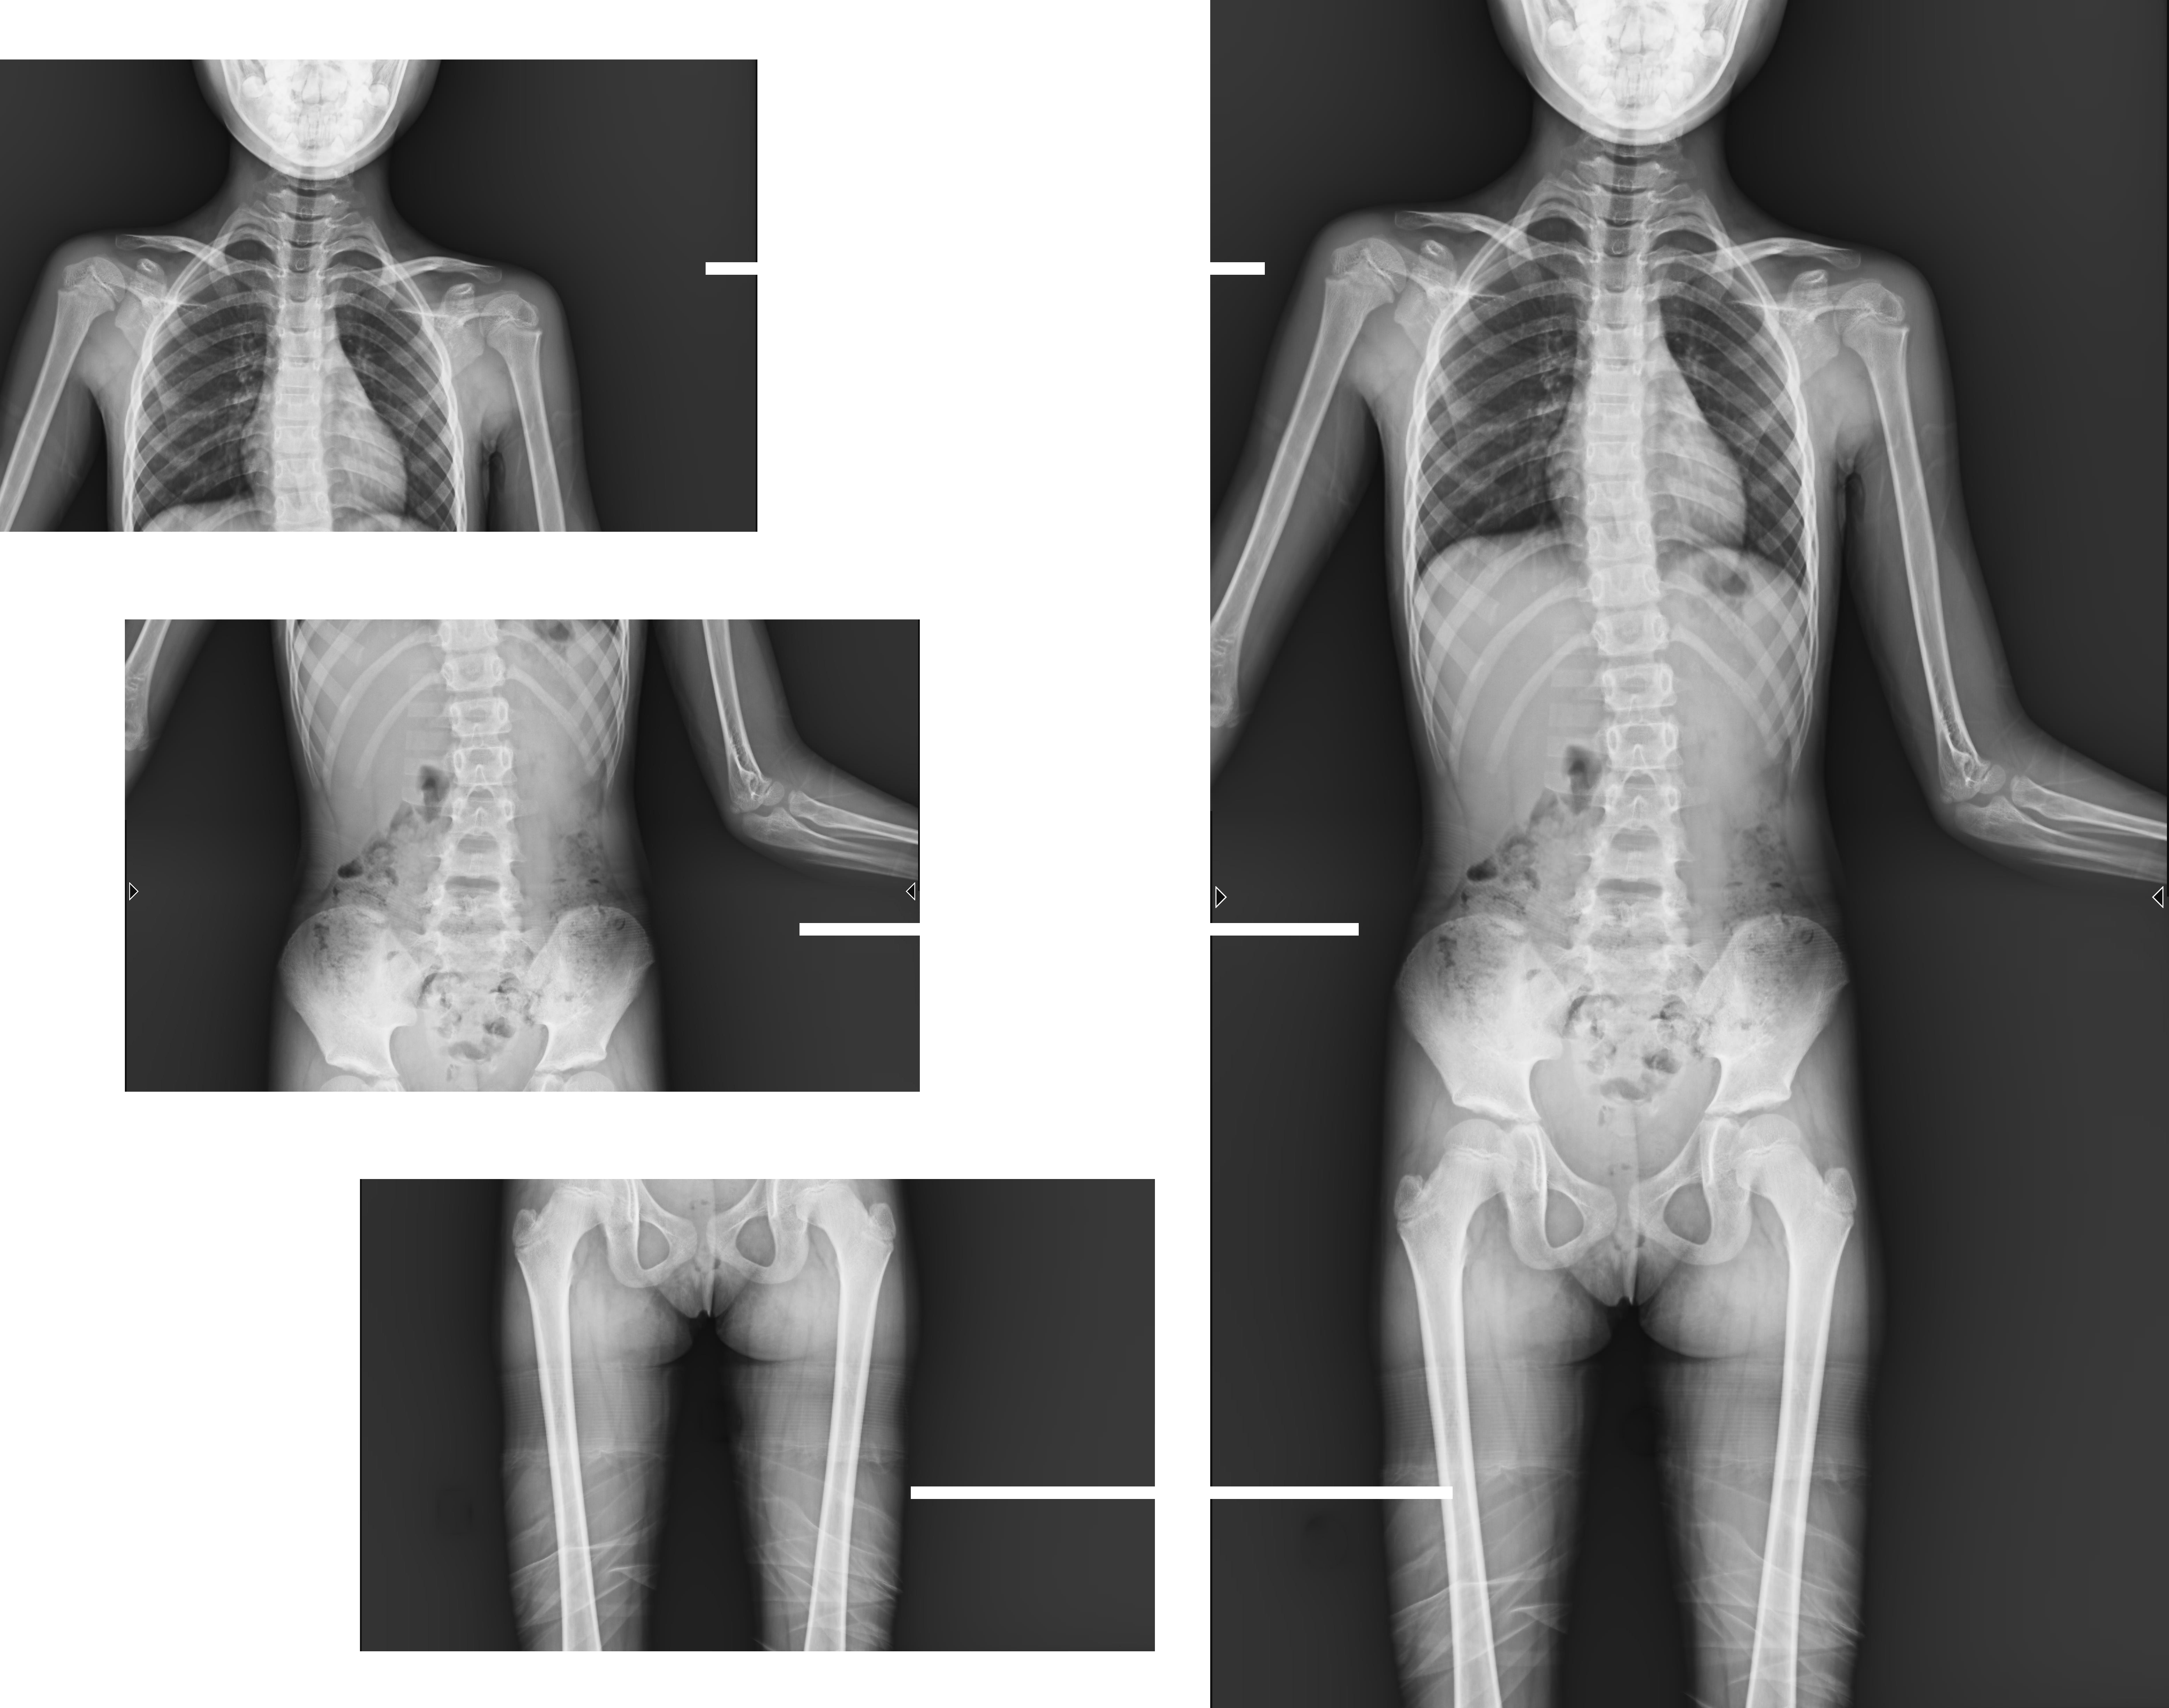

近年來,多發(fā)于青少年的脊柱側(cè)彎畸形,及骨性關(guān)節(jié)炎、風(fēng)濕性關(guān)節(jié)炎、雙下肢畸形(膝關(guān)節(jié)內(nèi)外翻、X型O型腿等)等骨科常見病發(fā)病率逐年增長,病癥常常累及下肢髖關(guān)節(jié)、膝關(guān)節(jié)、踝關(guān)節(jié)三個負(fù)重關(guān)節(jié),嚴(yán)重危害患者健康